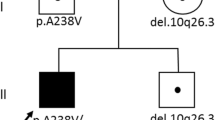

DNA from all four affected individuals was analyzed by WES. Since they were recruited at different times, each family was initially analyzed separately. Given the type of clinical presentation and sib recurrence in one family (Family 2), autosomal recessive inheritance was suspected. For this reason, we searched for rare homozygous or compound heterozygous variants within each family. In family 2, we selected only those candidate variants observed in both affected brothers (P2 and P3). The analysis of exome data for patient P1 uncovered two missense variants in exon 5 of the gene ECHS1 (NM_004092), a gene recently identified as a cause of LS: p.Thr180Ala and p.Gly195Ser. Screening of our in-house database allowed us to identify three additional LS-like patients carrying the p.Thr180Ala variant (Table 1). Re-analysis of the exome data of these four patients by focusing on variants or genes shared by more than one affected individual, allowed the identification of a second variant in the three additional patients. Only ECHS1 was mutated in all four patients (Table Supp1). None of the patients had other compound heterozygous or homozygous variants in nuclear genes associated with mitochondrial diseases including genes previously associated with LS (Chinnery 2000) (online updated version 2014). In addition, we did not identify other samples from our in-house rare disease database (more than 1000 samples) with homozygous or compound heterozygous variants in ECHS1, supporting the likely pathogenicity of these variants. To assess the possibility that the common mutation (p.Thr180Ala) arose from a single event, we looked at genotypes of known SNPs surrounding this shared variant. Polymorphisms were selected if they were reported in dbSNP138, had mapping quality of 60 and coverage higher than 10×. Carriers of this mutation shared a common 7.1 Mb haplotype (rs11245007-rs3737031), suggesting that the p.Thr180Ala variant in patients 1–4 derives from a single ancestral mutation (Table Supp2). This haplotype was not observed in 10 unrelated French-Canadian (20 chromosomes) control samples. In addition to this common variant, siblings P2 and P3 share a missense variant in exon 6 (p.Ala238Val) and P4 carries a missense variant in exon 4 (p.Gln159Arg) (Table 1). The missense variants p.Gly195Ser and p.Gln159Arg were recently reported in patients affected by a mitochondrial encephalopathy with clinical features very similar to our patients (Haack et al. 2015), suggesting the involvement of these variants in the disease. All four ECHS1 variants observed in our patients are extremely rare in control populations. In fact, they are not present in 1000 genomes, the 6500 NHLBI EVS, dbSNP138 or our in-house exome database, with the exception of missense p.Gln159Arg that is reported to be heterozygous in one individual from EVS and a second from our in-house database. Each of these variants are predicted to be pathogenic by at least one-prediction software (Table Supp 3) and observed at a conserved position in vertebrates (Fig. 3d). The missense variants p.Gln159Arg and p.Thr180Ala are not well conserved in C. elegans as arginine and alanine are the observed amino acids. Although valine is required for population growth in C. elegans, high concentration of this essential amino acid is not toxic (Perelman 2000). This difference in metabolism between human and C. elegans suggest that these amino acids changes may result in an accumulation of toxic metabolites in human that are tolerated in C. elegans. It has been previously reported that high damaging variants in human allele can be benign in other species, especially distantly related species such as nematodes, because of compensatory changes in other sites of the same protein or interacting partners (Jordan et al. 2010). All four missense variants are present in the large enoyl-CoA hydratase/isomerase domain, responsible for substrate binding and the catalytic activity of the enzyme, and are predicted to decrease protein stability (MuPro and Auto-Mute). Haack et al. have also reported a decrease ECHS1 protein level and enzyme activity in a patient carrying the p.Gln159Arg mutation, further supporting pathogenicity of the described variants (Haack et al. 2015).

To confirm the WES results, Sanger sequencing of genomic DNA was performed. All four heterozygous variants were confirmed in the corresponding affected patients (Fig. 3a–c). DNA from parents of P2 and P3 was available for segregation analysis and the variants were confirmed to be inherited in trans (Fig. 3a). DNA from the mother of patient P4 was also available and demonstrated that the mother is only carrying the p.T180A variant in a heterozygote state, suggesting an in trans transmission. Unfortunately, parental DNA was not available for patient P1 to assess the segregation of the variants. Since all patients share a common allele and haplotype corresponding to the variant p.Thr180Ala, we can infer that the second variant is likely to be on the other allele, and hence the variants were also transmitted in trans.